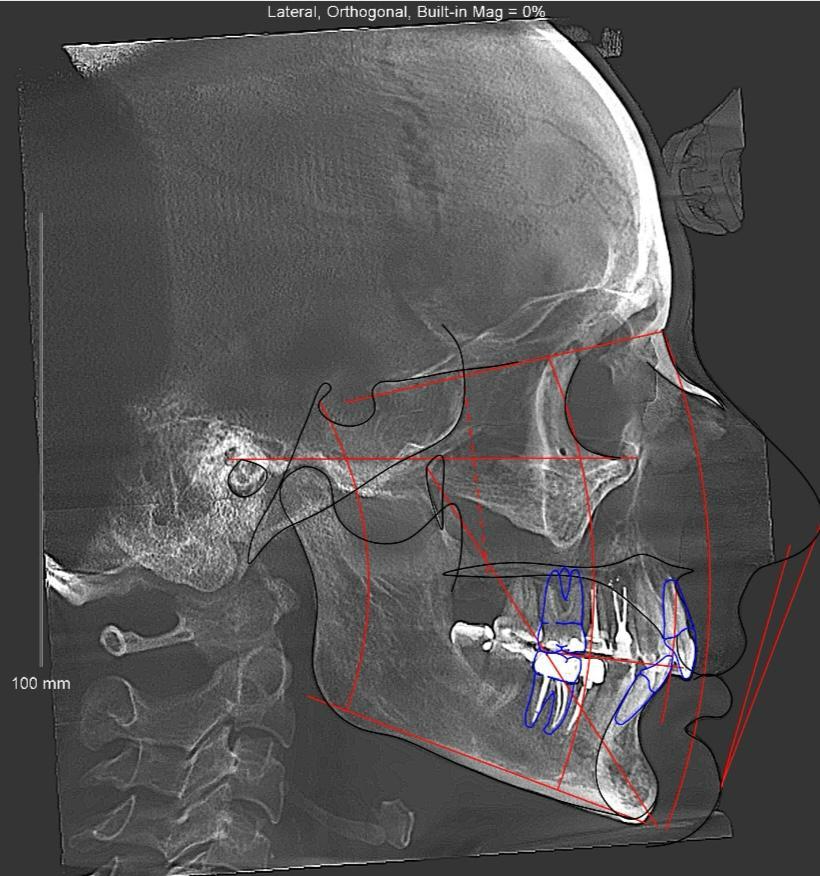

- Анализ данных. Точки ТРГ в ортодонтии помогают доктору провести детальный анализ и определить лечебный план. Данные отображаются на экране компьютера. Врач делает необходимые пометки, выделяет углы, рассчитывает расстояния между осями. Рентгенограмма распечатывается на бумаге, записывается на диск и передается клиенту.

2D-изображение объемного объекта требует профессиональной интерпретации. Ортодонты проводят детальный анализ полученных изображений, чтобы оценить расположение костей и их соотношение.

Расшифровка телерентгенограммы

Не рекомендуется, особенно в 1 триместре (1-13 недель) — период формирования органов плода, максимальная чувствительность к излучению. 2 и 3 триместр: только по жизненным показаниям (срочная операция, травма) с обязательной защитой живота свинцовым фартуком. Альтернатива: отложить плановое ортодонтическое лечение до родов и окончания грудного вскармливания, использовать старые снимки (если есть), если срочно нужна диагностика — МРТ (безопаснее рентгена). После родов: ТРГ можно делать сразу, грудное вскармливание — не противопоказание (излучение не накапливается в молоке).Что такое цефалометрический анализ ТРГ?

Цефалометрический анализ — математическая обработка телерентгенограммы для точной диагностики аномалий прикуса. Суть метода: на снимок наносят контуры костей и мягких тканей, отмечают ключевые анатомические точки (40-60 точек), проводят линии между точками, измеряют углы и расстояния, сравнивают полученные значения с нормой. Основные измерения: угол наклона верхней челюсти, угол наклона нижней челюсти, угол между челюстями, положение зубов относительно костной основы, профиль мягких тканей лица. Результат: цифровое описание типа прикуса и план коррекции. Выполняется ортодонтом вручную или с помощью специальных программ (Dolphin, OnyxCeph). Занимает 30-60 минут.Нужна ли ТРГ для установки брекетов?

На ТРГ отмечают анатомические точки и измеряют углы между ними. Основные точки: Nasion (переносица), Sella (центр турецкого седла), Orbitale (нижний край глазницы), Porion (верхняя точка слухового прохода), точка A (максимальная вогнутость верхней челюсти), точка B (максимальная вогнутость нижней челюсти), Pogonion (наиболее выступающая точка подбородка), Gnathion (самая нижняя точка подбородка). Основные углы: SNA (положение верхней челюсти относительно основания черепа, норма 82°), SNB (положение нижней челюсти, норма 80°), ANB (соотношение челюстей, норма 2°), угол наклона резцов, лицевой угол. Зачем: отклонения от нормы указывают на тип аномалии прикуса и способ коррекции.